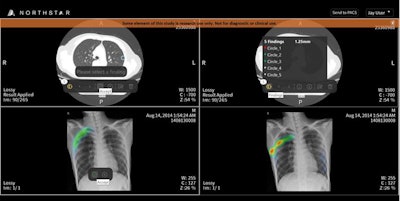

PACS software typically cannot readily accommodate AI algorithms. To make it easier to implement AI, the EnvoyAI platform now also includes TeraRecon's Northstar AI Explorer software, which enables users to view images and reports created by AI algorithms and to interact with them, according to the firm. Its user interface is compatible with all major PACS, electronic medical record, and enterprise viewing platforms.

A significant number of PACS companies have embedded Northstar AI Explorer into their PACS software and are distributing the EnvoyAI platform as part of their offerings, Sorenson said.